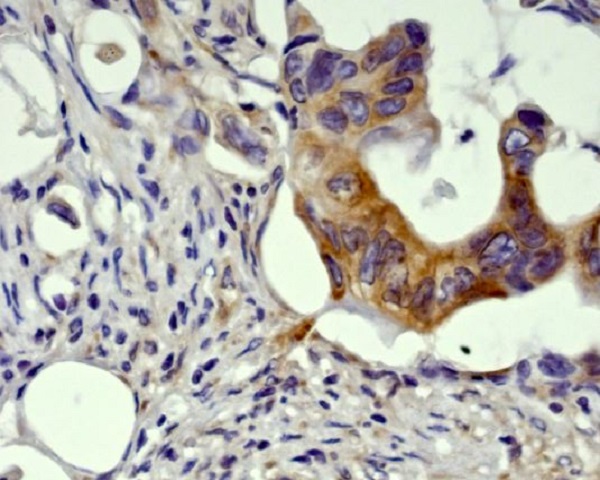

Immunohistochemical analysis of paraffin-embedded Human pancreatic cancer, using the Antibody.

Immunohistochemical analysis of paraffin-embedded Human pancreatic cancer, using the Antibody.